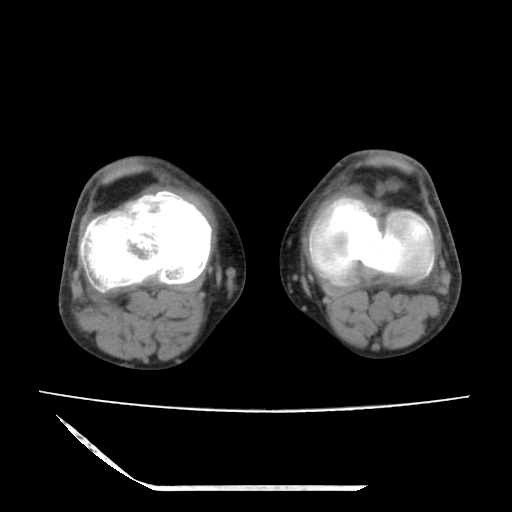

标题: CT13225:老年男性,左膝关节疼痛数月;请各位老师讨论。 [打印本页]

标题: CT13225:老年男性,左膝关节疼痛数月;请各位老师讨论。

骨质增生,骨性关节面硬化,关节积液,考虑退行性骨关节病

关节腔内少量积液,关节面退变。

双膝退变

骨质增生,骨性关节面硬化,关节间隙失常,关节积液,考虑退行性骨关节病.

这个病例诊断:退行性骨关节炎